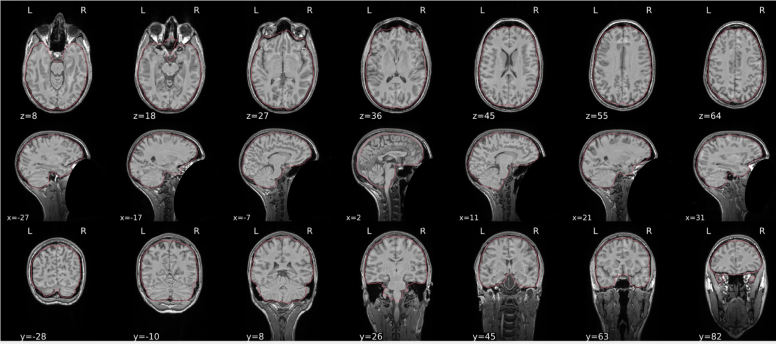

EPI spatial normalisation

This QC step shows the registration of the EPI image to MNI space.

Example of a good subject

- If the registration performed well, you should see an overlap (i.e., correspondence of structures) between the MNI template and the EPI registered to the MNI space.

- If parts of the brain are missing due to the scanner field of view, this is fine. For example, the cerebellum may be cut off for a participant with a large head.

Example of a bad subject

- In case of poor registration, you should see a misalignment of the EPI and the MNI template

Summary

| good | bad |

|---|---|

| Overlap (i.e. match of structures) between the MNI template and the EPI registered in the MNI space | Misalignment of the EPI and the MNI template |

| If parts of the brain are missing because the field of view of the scanner is limited, the EPI spatial normalisation does not have to be excluded e.g. cerebellum cut off in person with large head |

If parts of the brain are missing because the field of view of the scanner is limited, the EPI spatial normalisation does not have to be excluded (e.g. cerebellum cut off in person with large head)